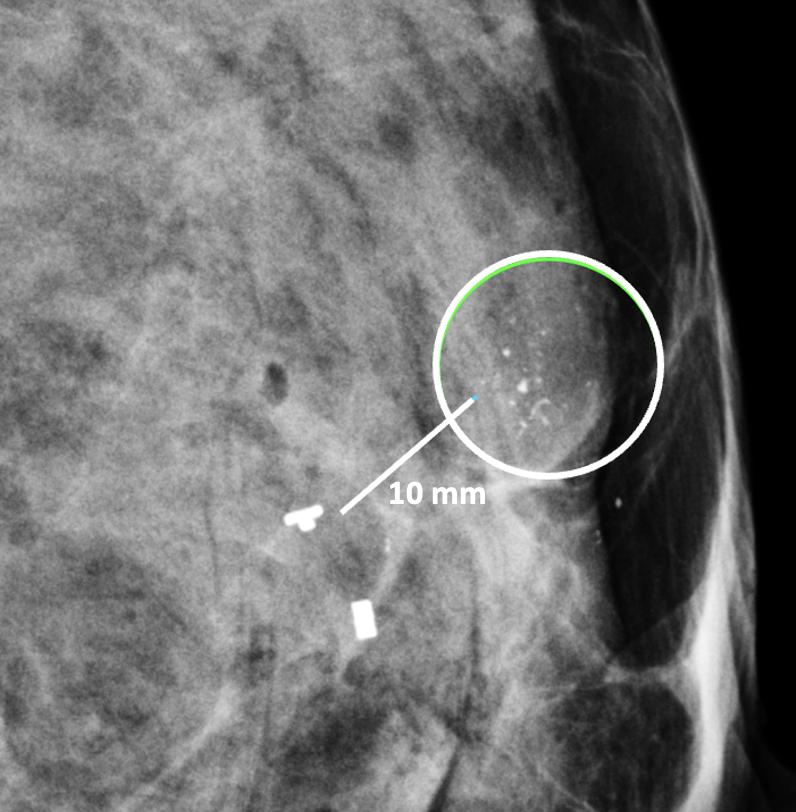

The second important consideration is marker migration or displacement. When a biopsy site marker is inserted at the time of the needle biopsy procedure, the marker may sometimes migrate or move several millimeters or centimeters along the needle tract away from its intended location (Image 14). Marker migration >10 mm occurs in 20% of diagnostic needle biopsy procedures and is more likely to occur with markers placed under mammogram or MRI-guidance, where the marker may shift away from its intended site when the breast is released from compression [20]. Bleeding or hematoma resulting from the needle biopsy can also displace a marker from its original location. Regardless of the cause, if adjustments are not made for marker migration, there is a reasonable possibility that the cancer will be incompletely ablated or missed altogether.

Image 14. Mammogram showing clip migration of two biopsy site markers displaced ~10 mm from microcalcifications (encircle). The lower, bar-shaped marker was placed at the time of the original diagnostic needle biopsy. The upper, T-shaped ultrasound-visible marker was subsequently inserted for localization of the calcifications, but also migrated ~10 mm from the intended location.